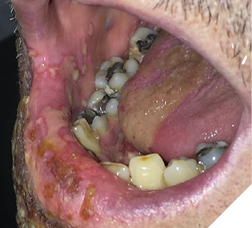

Mr. B., with advanced prostate cancer, complained of a terrible toothache. Clinically, tooth #47 revealed a large carious lesion. In addition, the patient had a herpes infection, both intraoral and extraoral (Fig. 2,3). The patient wanted the tooth extracted. The palliative care dentist in conjunction with the physician decided to treat the patient with an antibiotic and an antiviral prior to the extraction. The patient received amoxicillin (500 mg three times daily for 7 days), and acyclovir (400 mg 5 times daily for 7 days). To aid in pain relief a 50:50 suspension of diphenhydramine elixir with Kaopectate was applied to the lesions and a 2% viscous lidocaine rinse was also prescribed.6,7 The herpes simplex infection resolved and the tooth was extracted. The patient’s quality of life improved significantly and he spent his remaining days without oral pain.

Fig. 2

Fig. 3